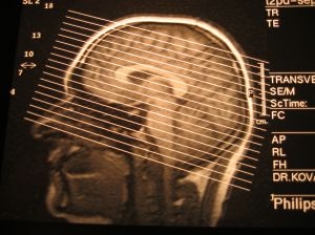

Head and neck cancer is defined as cancers developing from the soft tissue around the throat, mouth and tonsils, including the overlying skin.